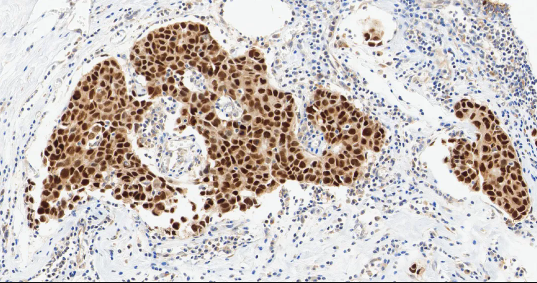

TTF-1

TTF-1——甲状腺转录因子-1,属于 NKX2 转录因子家族。

• 定位:细胞核。

• 功能:TTF-1 是调控肺组织和甲状腺器官特异性基因表达的核转录因子,对肺泡上皮细胞的终末分化和表面活性物质的分泌至关重要。

TTF-1 是关键的核转录因子,表达具有高度组织特异性。它在肺腺癌和甲状腺癌中高表达,是诊断这些原发癌的核心标志物[3]。其临床价值在于鉴别转移癌的原发部位:若 TTF-1 阳性,强烈提示肿瘤来源于肺或甲状腺。值得注意的是,肺鳞癌中 TTF-1 通常为阴性,需结合其他标志物来进一步确认。

图 2.人肺癌组织的 TTF-1 免疫组化分析。